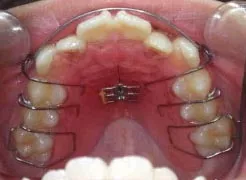

では、床矯正とはどのような矯正なのかと気になりますよね。床矯正は、入れ歯のような取り外しができる装置をお口の中に入れ、ご家庭でネジを巻いて顎の大きさを徐々に拡大していきます。幼児でも簡単にとりはずしができ、快適に矯正治療ができます。この装置は、以下のような特徴があります。

以下、当院で実施した床矯正の症例となります。

症例1

| 治療期間 | 11ヶ月(2021年6月〜2022年5月) |

| 費用 | 495,000円(税込) |

| リスクや副作用 | 成長期が終わった18歳以降に、2期矯正が必要になることがある |